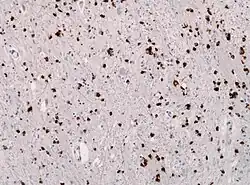

| Alpha-synuclein immunohistochemistry of the brain showing many glial inclusion bodies | |

Multiple system atrophy can be explained as cell loss and gliosis or a proliferation of astrocytes in damaged areas of the central nervous system. This damage forms a scar which is then termed a glial scar.[30] The presence of inclusion bodies known as Papp–Lantos bodies, in the movement, balance, and autonomic-control centres of the brain are the defining histopathologic hallmark of MSA.[31]

The major filamentous component of Papp-Lantos bodies, glial and neuronal cytoplasmic inclusions, is alpha-synuclein.[32] Mutations in this substance may play a role in the disease.[33] The conformation of the alpha-synuclein is different from that of alpha-synuclein in Lewy bodies.[3] The disease probably starts with an oligodendrogliopathy.[34] It has been proposed that the α-synuclein inclusions found in Oligodendrocytes result from the pruning and the engulfment of diseased axonal segments containing aggregated α-synuclein, i.e., of Lewy neurites [35]

Pathological diagnosis can only be made at autopsy by finding abundant glial cytoplasmic inclusions (GCIs) on histological specimens of the central nervous system.[48]

Contrary to most other synucleinopathies, which develop α-synuclein inclusions primarily in neuronal cell populations,[50] MSA presents with extensive pathological α-synuclein inclusions in the cytosol of oligodendrocytes (glial cytoplasmic inclusions), with limited pathology in neurons.[51] MSA also differs from other synucleinopathies in its regional pathological presentation, with α-synuclein positive inclusions detected predominantly in the striatum, midbrain, pons, medulla and cerebellum,[52][53] rather than the brainstem, limbic and cortical regions typically effected in Lewy inclusion diseases.[53] However, recent studies using novel, monoclonal antibodies specific for C-terminally truncated α-synuclein (αSynΔC) have now shown that neuronal α-synuclein pathology is more abundant than previously thought.[54][55] One group revealed robust α-synuclein pathology in the pontine nuclei and medullary inferior olivary nucleus upon histological analysis of neurological tissue from MSA patients.[54] Histopathological investigation on six cases of pathologically confirmed MSA, using antibodies directed at a variety of α-synuclein epitopes, revealed substantial variation in α-synuclein protein deposition across both cases and brain regions within cases, providing evidence for 'strains' of aggregated conformers that may differentially promote pathological prion-like spread.[56]